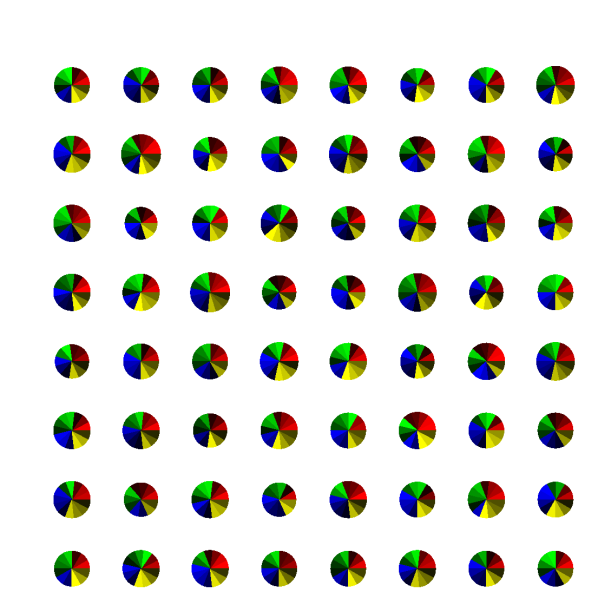

4.2 Comparison of undersampling patterns

Figure 5 shows the time efficiency computed for all the considered undersampling patterns as a function of acceleration factors and reciprocal of Discrepancy. All pattern generation techniques showed a decline in time efficiency with increasing acceleration factor. Some patterns, such as Regular and Sreg, showed a steeper decline than others. Note that these undersampling patterns also showed a difference between ηpMCsubscriptsuperscript𝜂𝑀𝐶𝑝\eta^{MC}_{p} and ηpsubscript𝜂𝑝\eta_{p} in the Monte Carlo simulation. The Halton pattern showed the lowest decline or the highest time efficiency with few exceptions.

Comparing the Discrepancy with time efficiency, the patterns with high Discrepancy showed lower time efficiency. Regular and Sreg were two patterns that showed the highest Discrepancy, also showed the lowest time efficiency. The other four patterns have a similar level of Discrepancy and showed a similar level of time efficiency. From these, the Halton pattern had the lowest Discrepancy and the highest time efficiency.

Given these results, the Halton pattern with acceleration factor 32 was chosen for the prospective acquisition, obtaining the best maps within 60 minutes of scan time.

Refer to caption

(a) ηpsubscript𝜂𝑝\eta_{p} computed for T1subscript𝑇1T_{1}

(b) ηpsubscript𝜂𝑝\eta_{p} computed for T2subscript𝑇2T_{2}

(c) Discrepancy

Fig. 5: (a and b) ηpsubscript𝜂𝑝\eta_{p} computed for T1subscript𝑇1T_{1} and T2subscript𝑇2T_{2} for all evaluated undersampling patterns and acceleration factors. (c) Discrepancy of downsampled undersampling patterns used for time efficiency computation.